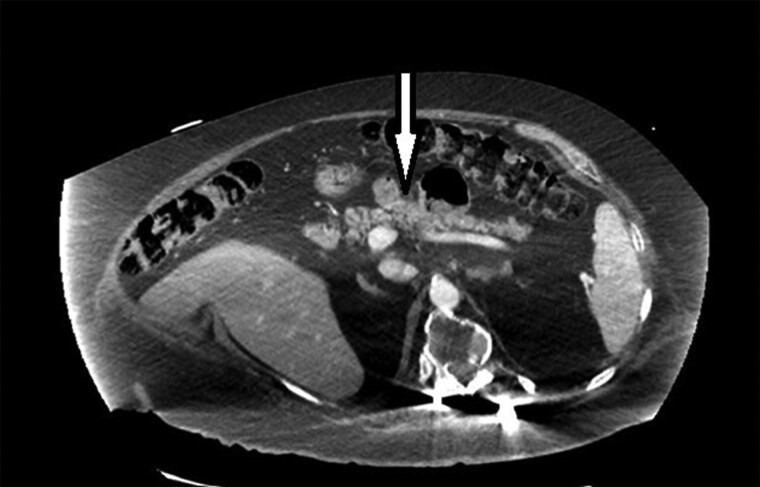

Endogenous hyperinsulinemia hypoglycemia has numerous etiologies. The objective of this report is to describe a patient with severe hyperinsulinemic hypoglycemia with no known history of diabetes or hypoglycemia who presented with acute altered mental status. Blood glucose was noted to be 40 mg/dL (2.22 mmol/L) (reference range 65-125 mg/dL; 3.61-6.94 mmol/L). The patient's sulfonylurea screen was negative. Following 1 mg glucagon injection, the patient's glucose did not improve, a response inconsistent with insulinoma. Imaging studies of the pancreas did not show pancreatic mass. Two weeks before the presentation, the patient started on tramadol for back pain with the dose increased 3 days prior to presentation. The patient's hypoglycemia resolved and returned to baseline 4 days after the initial presentation. Tramadol has been reported to cause hypoglycemia, especially in the elderly population. Tramadol may act on μ receptors on β cells to upregulate insulin secretion. When approaching a patient with endogenous hyperinsulinemia, one should consider tramadol or other analgesics as a possible etiology.